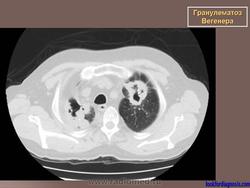

Поражение легкихразвивается у 3/4 больных, проявляется формированием инфильтратов, которые могут распадаться и образовывать полости. Иногда наблюдается плеврит.

При генерализованной форме ........ картина пневмонии с наклонностью к абсцедированию и появлению плеврального выпота.

Рентгенологическое исследование легких: инфильтраты, часто с распадом и образованием полостей, редко - плеврит.